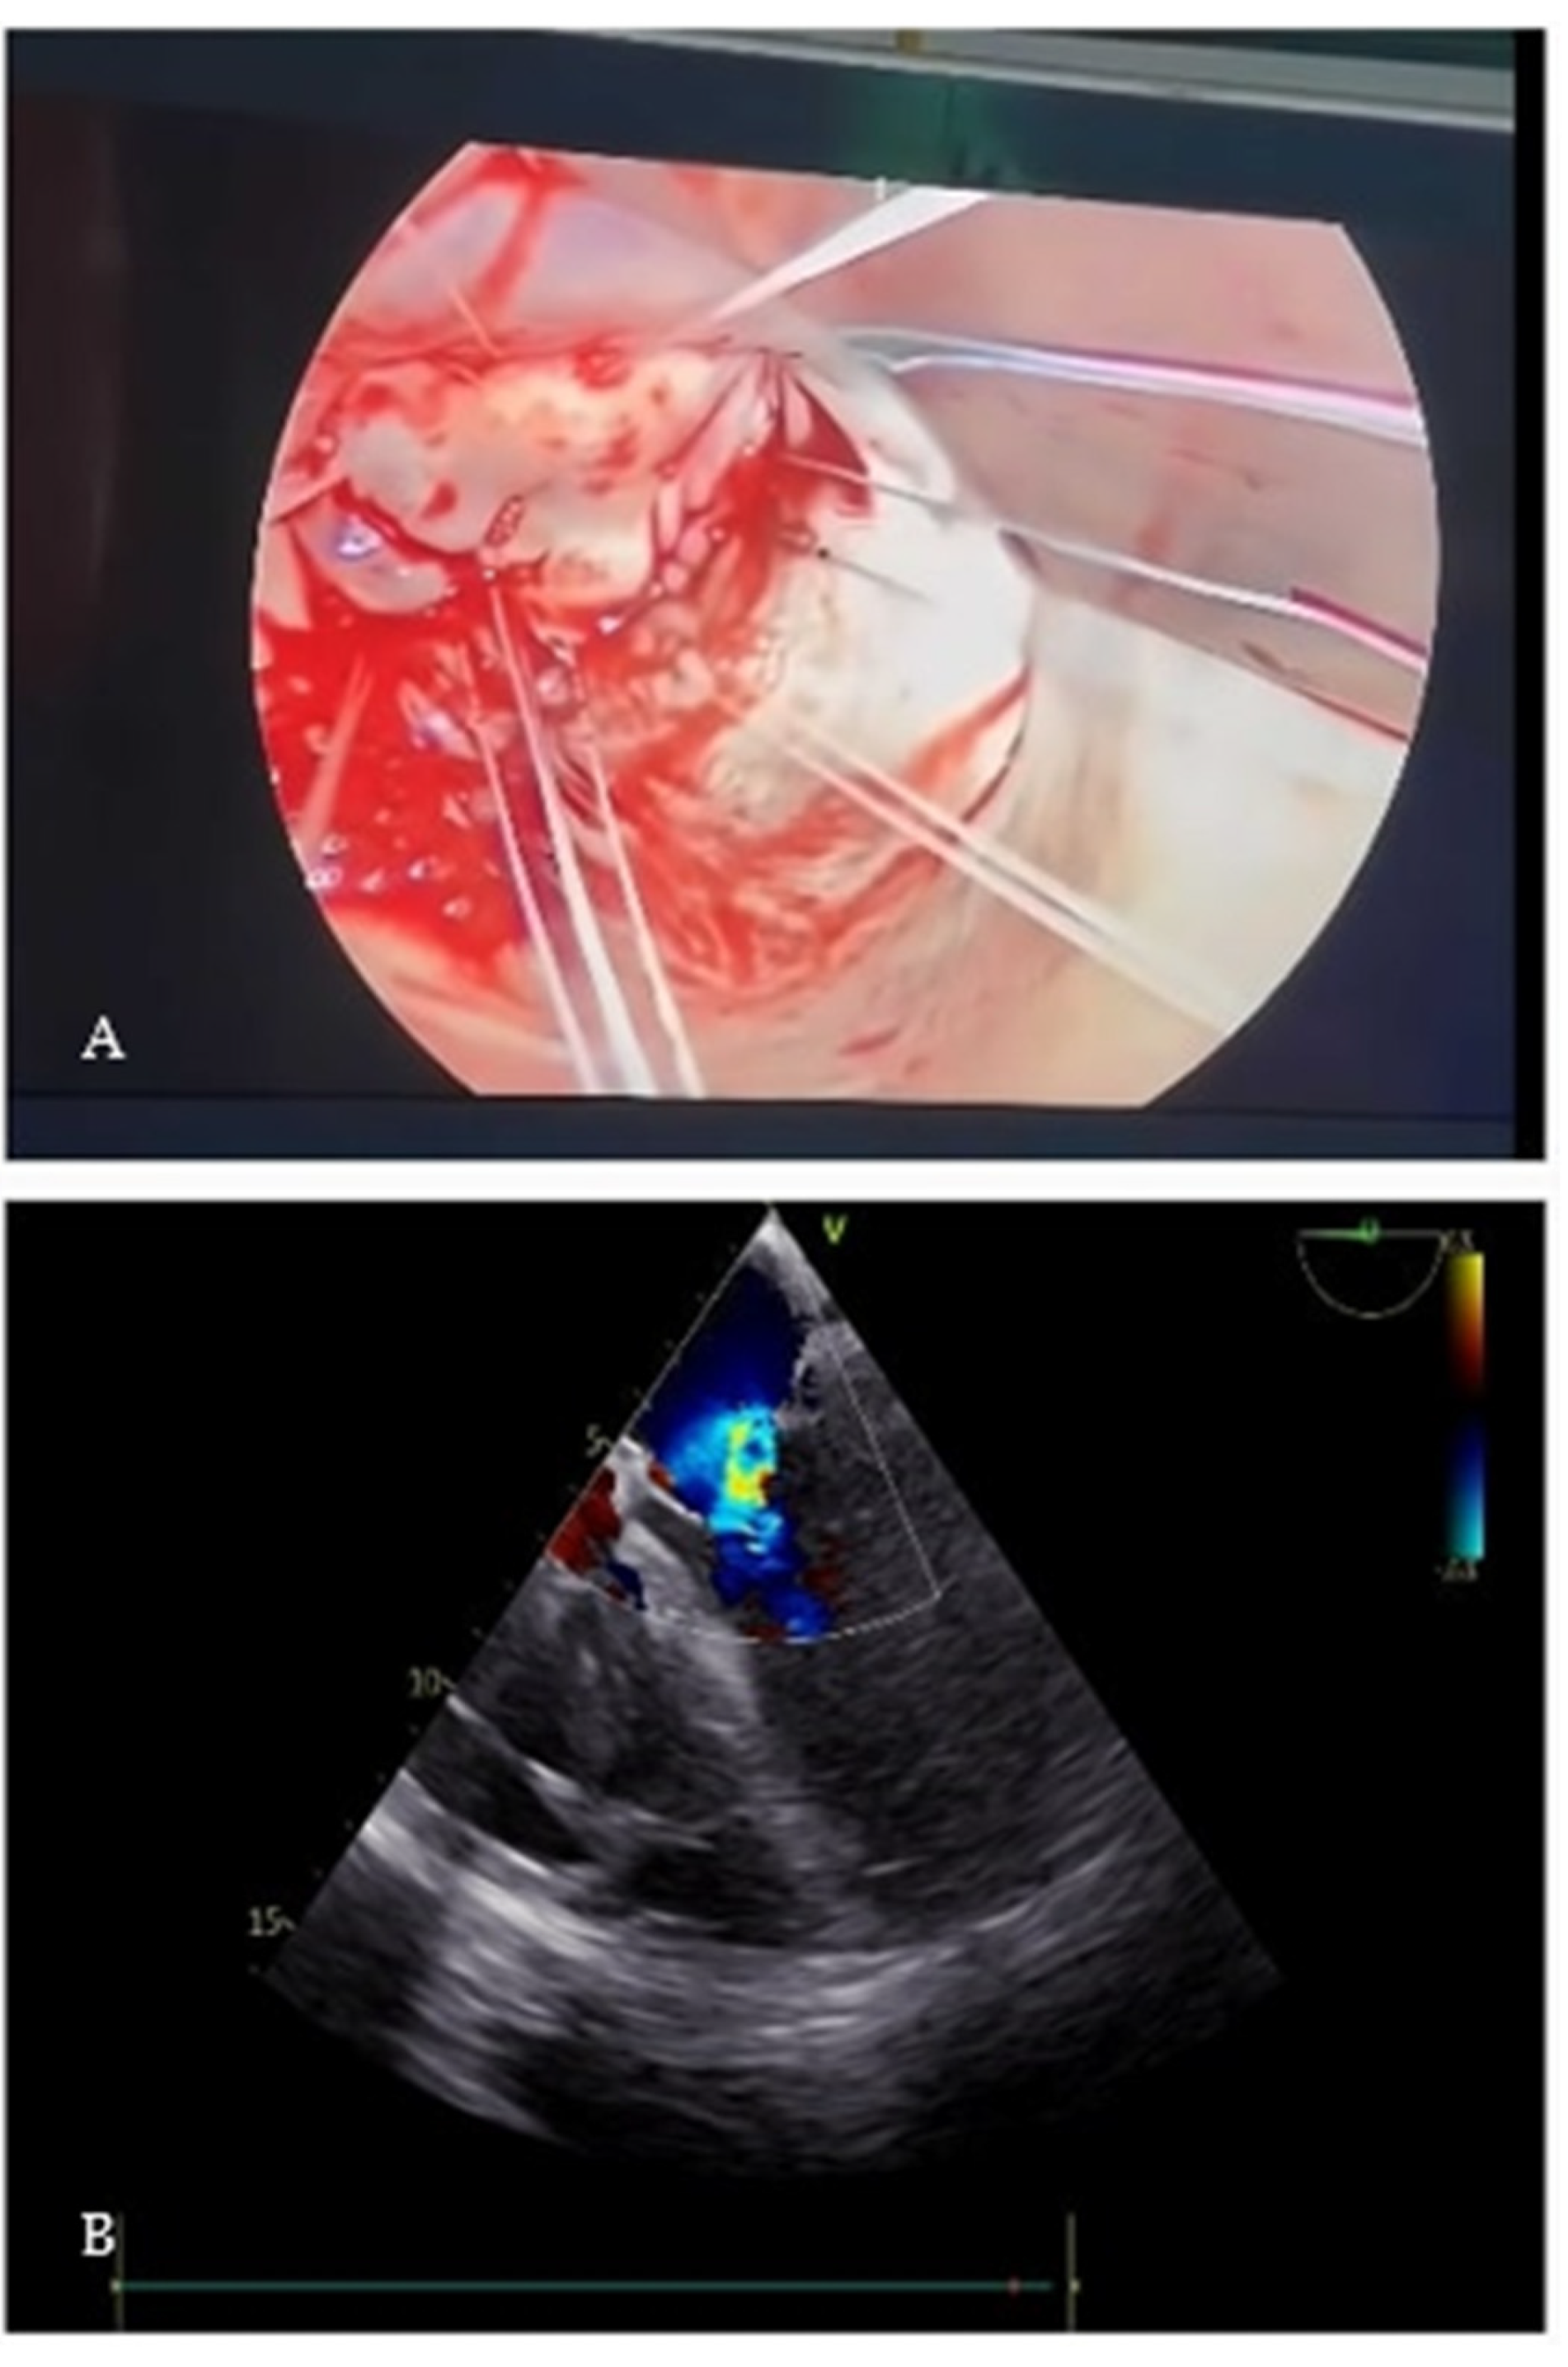

2. Case Presentation